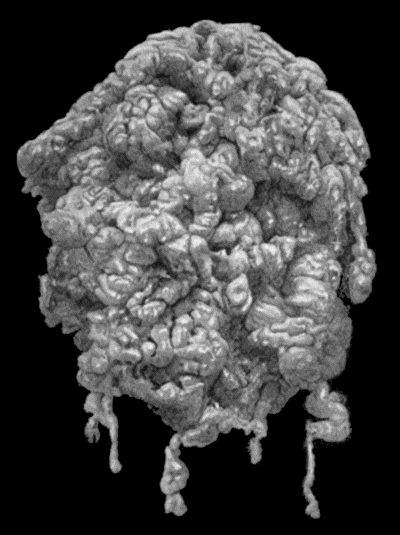

| 112. | Ossification in Muscles of Trunk in generalised Ossifying Myositis | 419 |

| 113. | Hydrops of Prepatellar Bursa | 427 |